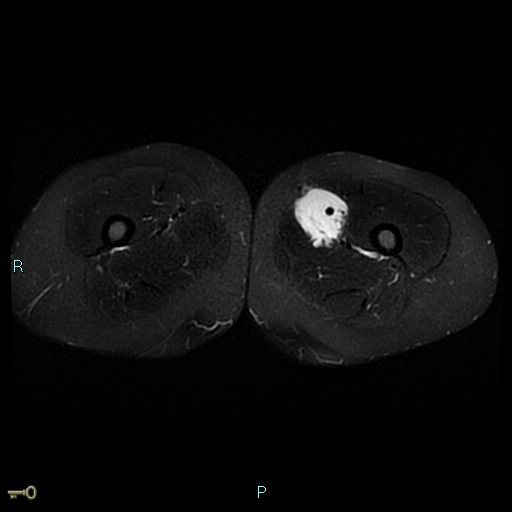

Sarcoma cơ vân (Rhabdomyosarcoma - RMS)